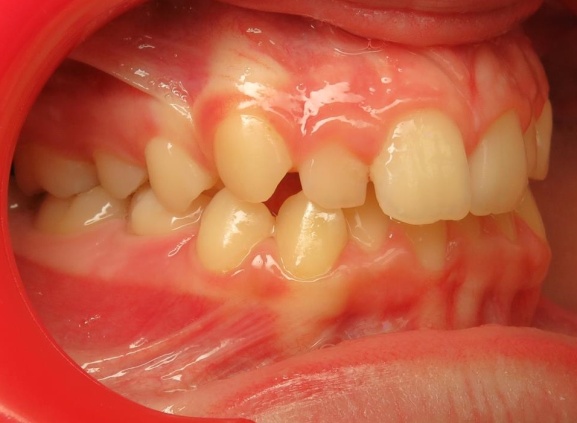

4 - Évolution du visage avant et après traitement.

Le profil est clairement amélioré. Ce traitement est une réussite à la fois fonctionnelle, en rétablissant une occlusion stable, et esthétique, avec un menton bien projeté. L’analyse céphalométrique de Delaire avait anticipé cette croissance favorable, confirmée par le résultat final conforme au diagnostic initial.